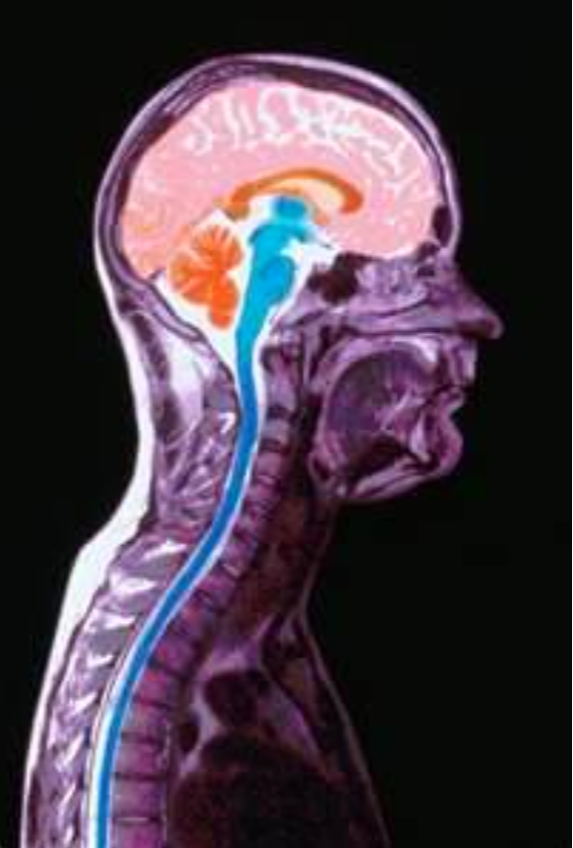

3. SPINALÂ THERMOGRAPHY

Chiropractic was founded on its ability to restore nerve function. However, most practitioners lack an effective tool for evaluating their success in correcting patient nerve function.

PRS utilizes one of the most reliable spinal nerve function tests. Recent studies by the American Academy of neurosurgeons have found spinal Thermography to be over 80% accurate for evaluating spinal nerve function.

This tool is one of the foundations in our system of subluxation correction, because it allows you to almost instantly measure the effect of your adjustment on your patientâs nerve function. When used with our pattern analysis software, it is an invaluable tool for clinical use.